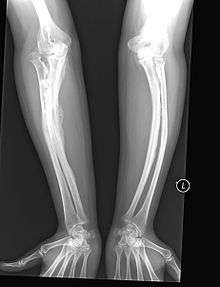

OI Type V leads to calcification of the membrane between the two forearm bones, making it difficult to turn the wrist. Another symptom is abnormally large amounts of repair tissue (hyperplasic callus) at the site of fractures. Other features of this condition include radial head dislocation, long bone bowing, and mixed hearing loss.